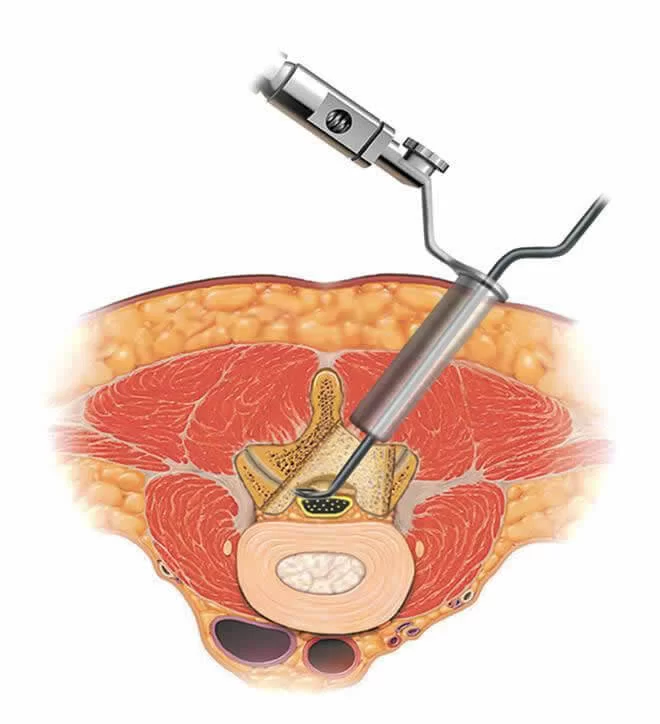

Η χειρουργική θεραπεία της σπονδυλικής στένωσης είναι η αποσυμπίεση. Προτιμούμε ελάχιστα επεμβατικές μεθόδους μια και προσφέρουν πολλά πλεονεκτήματα σε σχέση με τις κλασσικές (ανοιχτές) μεθόδους όπως για παράδειγμα μικρή τομή (περίπου 1-1,5 εκ), μικρό χρόνο νοσηλείας, μηδαμινή απώλεια αίματος και μηδαμινό κίνδυνο φλεγμονής. Η ελάχιστα επεμβατική αποσυμπίεση του σπονδυλικού σωλήνα γίνεται με τη βοήθεια του μικροσκοπίου ή του ενδοσκοπίου (βλ. παρακάτω βίντεο).

Το τελικό αποτέλεσμα είναι η πλήρης αποσυμπίεση των νεύρων και η άμεση ανακούφιση των συμπτωμάτων του ασθενούς και κυρίως του πόνου ή του αισθήματος βάρους και αδυναμίας στα πόδια κατά τη βάδιση (Εικόνα 4).

Η καλύτερη χειρουργική τεχνική είναι αυτή που λύνει τα προβλήματα του ασθενούς αποτελεσματικά και με ασφάλεια. Προσωπικά όμως, βλέπω πολλά και σημαντικά πλεονεκτήματα στις λεγόμενες “ελάχιστα επεμβατικές τεχνικές“. Με τη διαδερμική αποσυμπίεση (over-the-top technique), αποσυμπιέζονται και οι δύο πλευρές του σπονδυλικού σωλήνα χωρίς όμως να χρειάζεται ο χειρουργός να ανοίξει και από τις δύο πλευρές. Όλη η αποσυμπίεση γίνεται μέσα από μια μικρή τομή 1,5 εκ. Μ’ αυτό τον τρόπο προστατεύονται πολλές υγιείς δομές (οστά, σύνδεσμοι, αρθρώσεις κλπ) οι οποίες συμβάλουν στη σταθερότητα της σπονδυλικής στήλης.